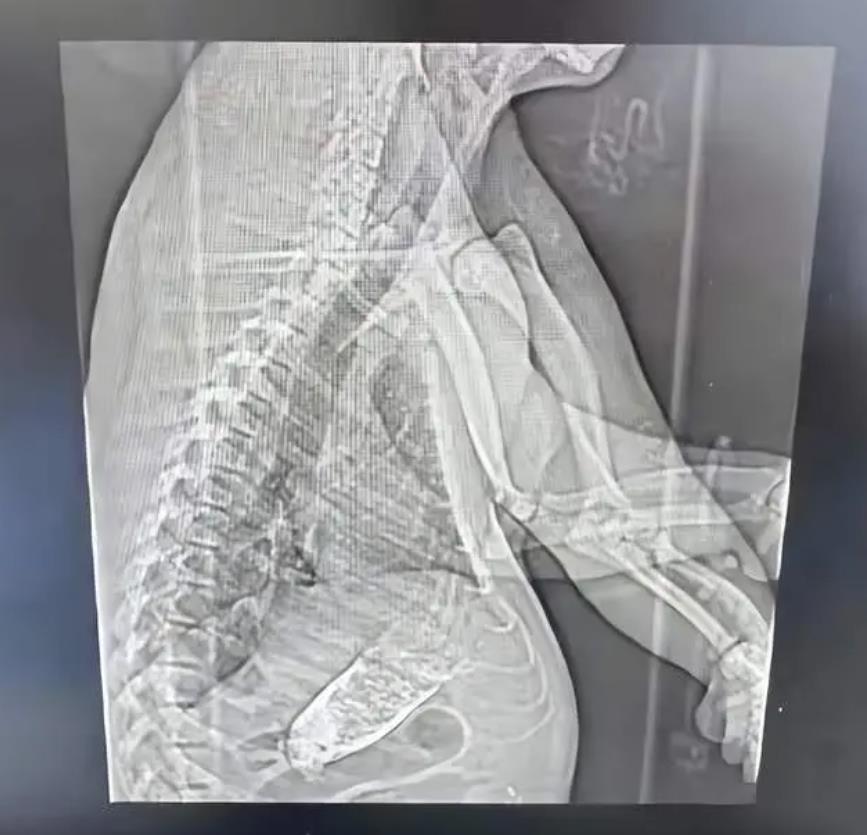

昨晚(2月28日),一則上海三甲醫院CT信息單引發熱議,在病人姓名一欄寫着「熊貓」。發帖網友稱,被檢查的是上海野生動物園熊貓。據內地媒體報道,經過和上海野生動物園核實了解到,居住在上海野生動物園裏的大熊貓「七七」近日因腸梗阻緊急送往上海仁濟醫院南院檢查,目前正全力救治。

不少熊貓粉絲表示,腸梗阻對熊貓來說是很危險的情況,希望七七這次一定要平安康復。據上海野生動物園的工作人員表示,熊貓的確被送去醫院接受檢查了,具體情況不清楚。「我們園區有獸醫全程陪同,目前情況來看,熊貓的身體狀況應該是沒什麼問題。」